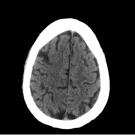

Catherine Anderson-Quinones, BM; Kinza Khan, BA; Sonal Khedkar, BS ; Andrew Wilner, MD; Jay Patel, DPM, MD

The patient was a 48-year-old man who presented with headache, left eye ptosis, a dilated pupil, and tooth pain for 10 days duration. They had a history of hypertension and poorly controlled type 2...

A 67-year-old man who developed new onset neurological symptoms was found to have bilateral internal carotid artery (ICA) pseudoaneurysms on computed tomography angiography.